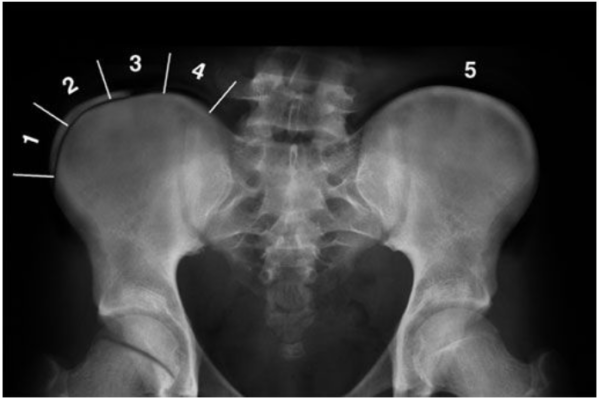

Verstehen der Risser-Skala Skoliose: Beurteilung von Wachstum und Verkrümmung der Wirbelsäule

Learn about the Risser Scale in scoliosis, a crucial tool for evaluating spinal growth and [...]